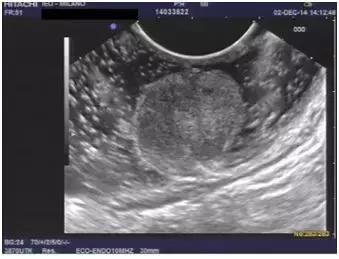

6、 诊断直肠神经内分泌瘤,需要做超声内镜么?

答:直径超过1cm的直肠神经内分泌瘤需要超声内镜检查明确侵犯深度和排除肠周淋巴结转移,1cm以内的可以不做。

本图截取于国外文献